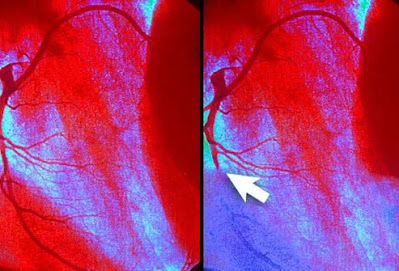

Έλεγχος καρδιακών παθήσεων: Καρδιακός καθετηριασμός

Ο καρδιακός καθετηριασμός μπορεί να βοηθήσει τους γιατρούς να βρουν μπλοκαρίσματα στις αρτηρίες που μπορεί να προκαλέσουν καρδιακή προσβολή.

Η πλάκα στις καρδιακές αρτηρίες μπορεί να είναι ένα σοβαρό πρόβλημα, ακόμη και απειλητικό για τη ζωή, σε ορισμένους ασθενείς. Η διάγνωση της απόφραξης της πλάκας των στεφανιαίων αρτηριών και η θεραπεία των αποφράξεων έχει βελτιώσει τη ζωή πολλών ασθενών με στεφανιαία νόσο. Ο καρδιακός καθετηριασμός είναι μια τεχνική που μπορεί να παρέχει τόσο διαγνωστικές πληροφορίες όσο και θεραπευτική μεθοδολογία σε μία διαδικασία. Η τεχνική είναι επεμβατική και μπορεί να χρησιμοποιηθεί για τον εντοπισμό αποφράξεων στην καρδιά που προκαλούν καρδιακές προσβολές.

Πώς λειτουργεί ο καρδιακός καθετηριασμός

Ένας λεπτός σωλήνας τοποθετείται σε ένα αιμοφόρο αγγείο στο πόδι ή το χέρι και περνάει με σπείρωμα στην καρδιά και στο άνοιγμα μιας στεφανιαίας αρτηρίας.

Η βαφή μπαίνει στο σωλήνα και μπαίνει στην αρτηρία.

Ένα ειδικό μηχάνημα ακτίνων Χ απεικονίζει τη βαφή, που δείχνει στένωση ή απόφραξη της αρτηρίας.

Ο ίδιος σωλήνας μπορεί να χρησιμοποιηθεί με ειδικές άκρες για το άνοιγμα της στεφανιαίας αρτηρίας με αγγειοπλαστική (το μικρό μπαλόνι είναι φουσκωμένο) ή να χρησιμοποιηθεί για την τοποθέτηση ενός συρμάτινου πλέγματος (stent) που διαστέλλεται για να κρατήσει την αρτηρία ανοιχτή.